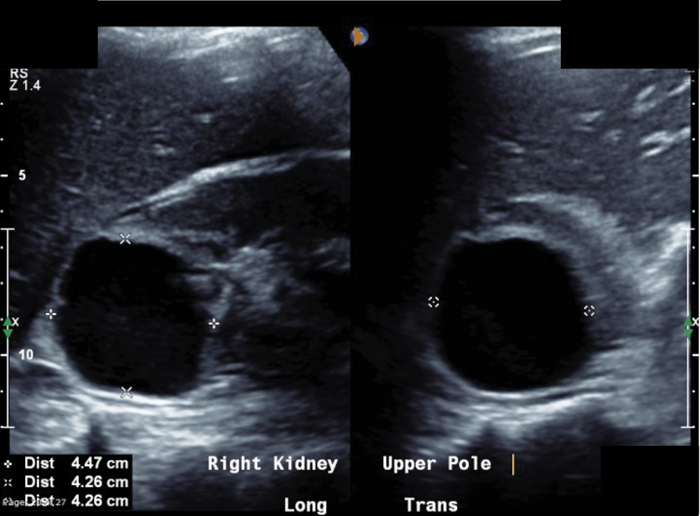

A 34-year-old lady is referred from the medics with right-sided loin pain and urosepsis. An initial ultrasound scan was arranged, followed by a subsequent CT scan. These scans did not show any renal / ureteric stone, but selected images are shown to the left.

- What do the images show?

A well-defined cystic structure in the upper pole of the right kidney. The cystic structure had calcification within the wall. CT demonstrated a fluid density mass within the cyst, with an irregular coarse foci of wall calcification. There is a solitary gas locule within the superior aspect of the cyst.